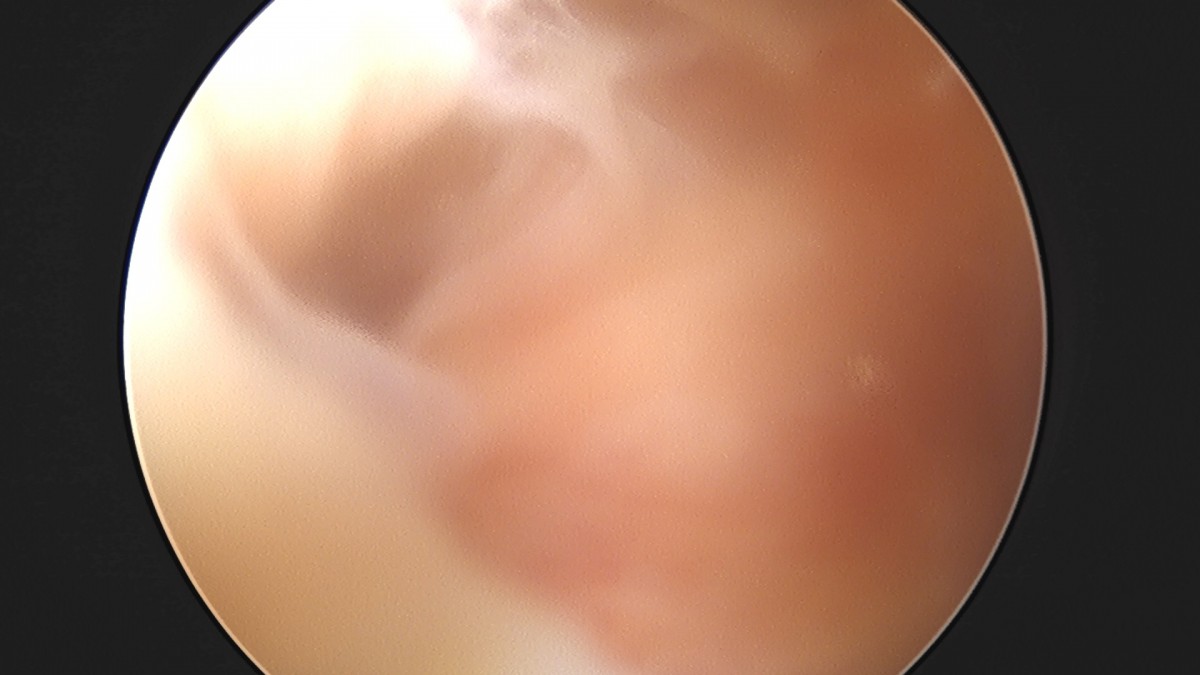

이재상원장님 무릎 전방십자인대 재건술 김태O 환자

dae765e4d9ac96aee867c9d6292d8784_1758007426_8923.jpg